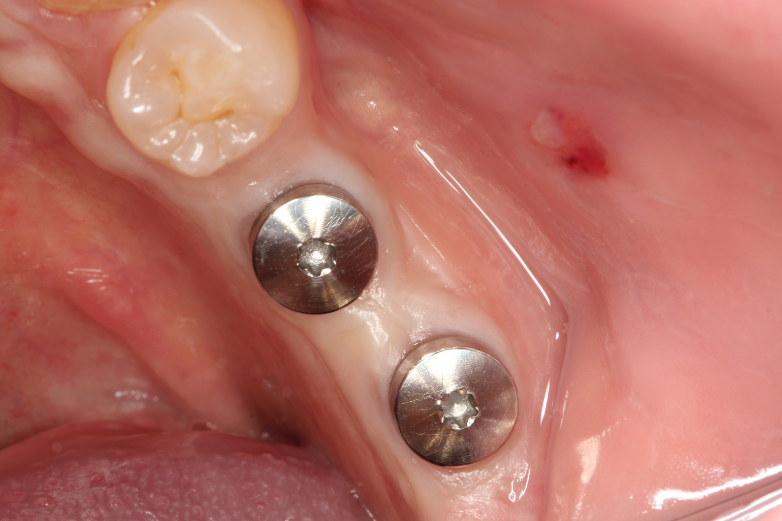

Posterior screw retained implants